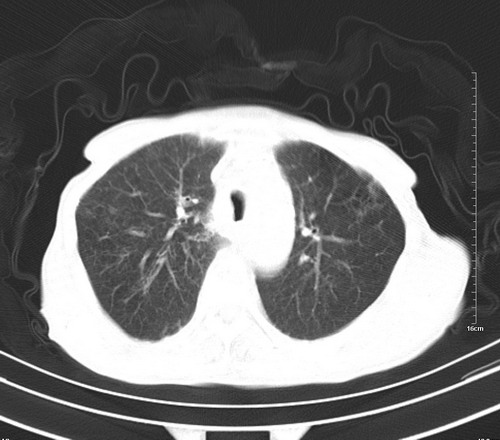

病人,女,79岁,主要因腹疼二月入院,彩超,肝,胆,脾,未见异常,胸透上消化道造影未见异常,化验白细胞增高,内科医生让做胸部ct检查,因为熟人多做了腹部(外科会诊考虑胆囊炎).现ct片如下请假各位战友.

肺癌,纵隔淋巴结转移,肝左叶病变考虑为转移病灶。

后中纵隔团块影,伴气管、食道受压移位,首先考虑转移瘤,肝s5段低密度灶。建议增强检查,另外其结肠是否有问题请提供,右肺部分肺叶局限含气增多,考虑局限肺气肿。

建议强化检查,考虑纵隔型肺癌,小细胞可能性大。

后中纵隔淋巴结肿大,首先考虑转移瘤。